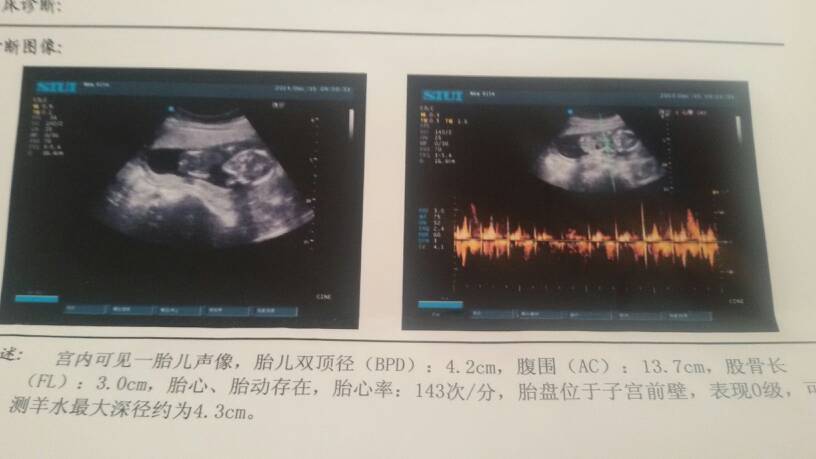

亲,看看有没有会看的帮我看看是男宝女宝呵呵 点击展开 155*****345_AYU1 2014-12-16 18:25 为您推荐: 其他回答 你好,根据图片不能判断是男是女,正常情况下想知道是男是女的方式就是B超检测和羊水穿刺,较为准确和科学,不管男孩女孩宝宝健康就好。 cn#BBLQpuQVuf 2014-12-16 18:43 相关问题 亲们现在能看出是男宝,女宝吗?!?!帮我看看呗 有没有经验的宝妈帮我看看是男宝女宝啊! 请大家帮我看看是男宝女宝?肚子特别向下的 还麻烦大家帮俺的宝宝起个好听的名字哦?谢谢喽 么么哒